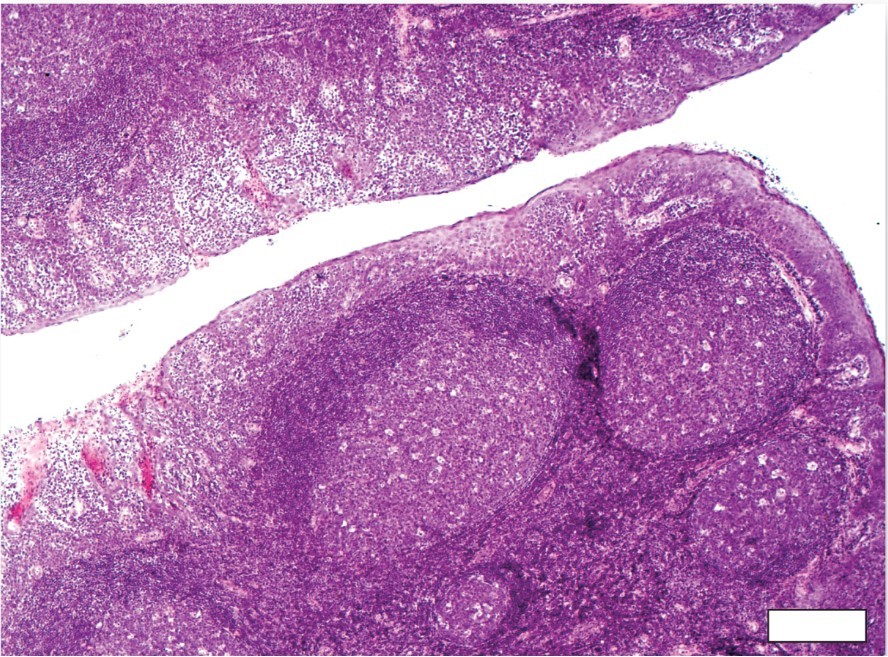

Lingual Tonsils

a collection of lymphatic tissue located in the lamina propria of the root of the tongue. This lymphatic tissue consists of the lymphatic nodules rich in cells of the immune system (immunocytes).

Lingual Tonsils (Histology)